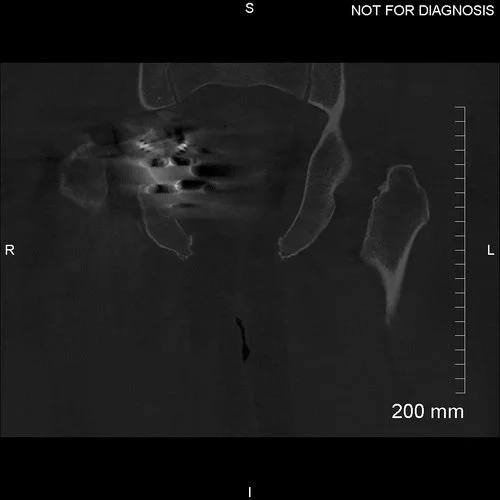

Coronal CT scan was used to plan the custom acetabular implant. Removal of the previous metal components allowed for better characterisation of the acetabular bone.

3D CT reconstruction showing the hemipelvic defect